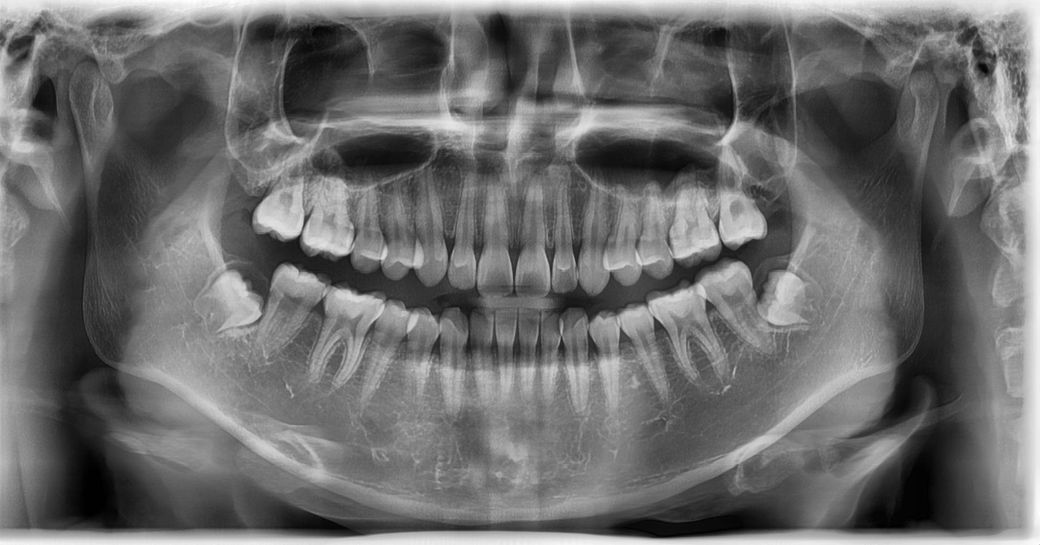

• 2번 째 사진

사진으로 봤을 때 송곤이 치아 뿌리에 각도는 이상이 없는 것으로 보입니다. 또한 파노라마 사진은 이 차적으로 보는 사진이기 때문에 정확한 뿌리의 각도를 보인다기보다 경우에 따라서는 겹쳐 보이는 것처럼 느껴질 수 있습니다.

그다지 쓰러져있어 보이지 않고 쓰러져 있다고 하더라도 특별히 치료를 할 수 있는 건 없습니다.

사진상으로 보면 쓰러져 잇지만 교합상태가 괜찮으면 크게 문제가 되는건 없고 교합이 안좋으면 치아들이 부딪히면서 불편감이 생길수 있습니다.

1. 교정 시 치아 머리 부분만 움직여 치축이 틀어진 것 같습니다 이미 배열이 완료되어 공간이 닫힌 경우 치근 이동 개선이 쉽지는 않습니다

2. 엑스레이상 거의 붙어있을정도로 근접해보여도 왜곡이 있어서 그럴 수 있습니다

3. 실제로 두 치근이 너무 근접하면 치근흡수의 가능성이 있고, 치아가 힘을 받는 장축방향이 수직이 아니면서 힘을 과도하게 받을 수도 있습니다